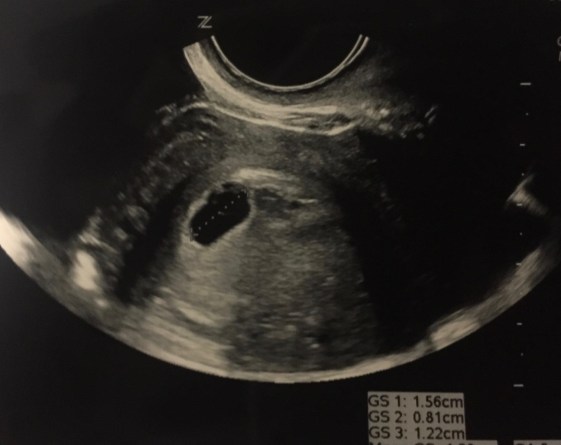

One of my worst nightmares happened at around 5 1/2 weeks into the pregnancy when I started bleeding. The first thing that came to my mind was miscarriage, miscarriage, miscarriage. I called my doctors office right away and told them what was going on. They went through a laundry list of questions to see if I could have been miscarrying. The strange thing about this incident was that I did not have any cramping. The bleeding was more than spotting and went from brown to red colored. The doctors office scheduled me an appointment for that afternoon. I called my hubby to update him with what was happening and he rushed home from work to take me to the appointment. The time in the waiting room felt like eternity. All I wanted was one answer. Is our little babe okay? The ultrasound results ended up being that the fetal tissue that attaches to the cervical wall does not always connect 100% and can get a leaky blood vessel. We were not able to hear the heartbeat because it was still too early BUT we were able to see it. The way my hubby’s face lit up when we saw the heartbeat is indescribable. I wish I got it on video. We were told the baby was developing “textbook style”. That news made us more confident in this pregnancy. We scheduled a follow up appointment for a week later. In the mean time, I bled here and there. The only pregnancy symptoms during this time were exhaustion and breast tenderness. Every night after we ate dinner I would lie down on our sofa and fall asleep around 7:30. Growing tiny humans is exhausting.